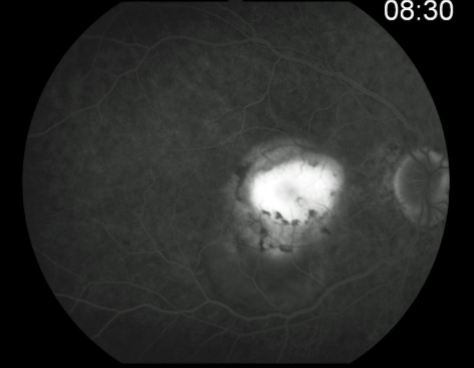

classic CNV

classic & occult CNV

type 2 MNV

MNV is now b/t neurosensory retina & RPE making the IVFA more obvious & well defined

IVFA shows lacy, well-group area of neovascularization

hyperfluorescent early in study

late leakage

lacy early fill of the MNV during the choroidal & arterial filling phase

may have hypofluorescence corresponding to RPE hyperpigmentation & blood in the outline of the MNV